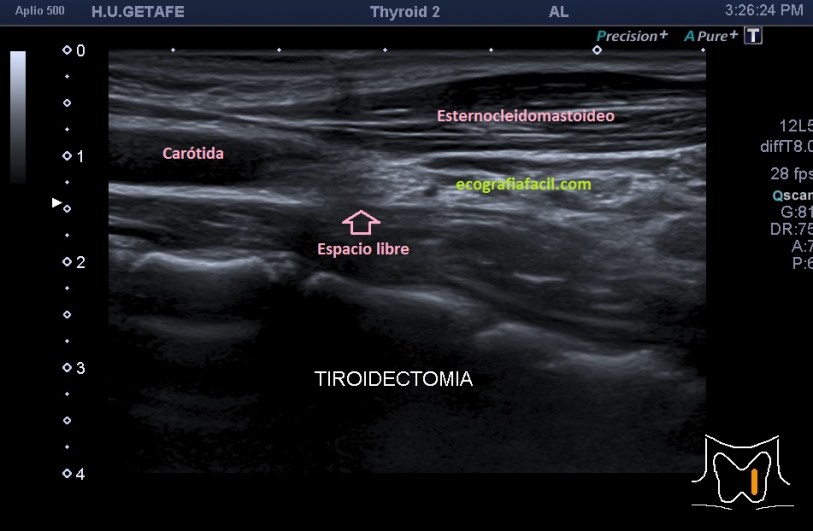

cuando hacemos un tiroidectomizado, vemos esto:

Quiero que veas las dos imágenes y compares.

Lo más importante, saber cómo es la «normalidad» de una región tiroidectomizada, te la dejo en las dos siguientes imágenes, veremos una zona hiperecogénica correspondiente a la grasa que ocupa el espacio que ya no ocupa el tiroides. Cuando el paciente es diagnosticado de ca de tiroides suele realizarse tiroidectomía total.